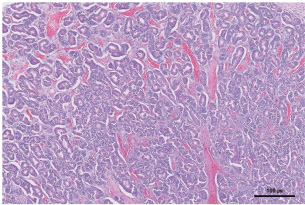

An 11-year-old intact male Siberian Husky was presented in acute hypovolemic shock. On physical examination, the patient was lethargic and exhibited tachycardia, tachypnea, and hypotension, with a recorded systolic/diastolic blood pressure of 58/31 mmHg. Abdominal radiographs were not diagnostic due to the loss of serosal detail secondary to intra-abdominal fluid accumulation. Hematologic evaluation revealed microcytic (mean cell volume, 58.4 fL; reference range, 61.6–73.5 fL) and normochromic (mean corpuscular hemoglobin concentration, 30 g/dl; reference range, 32–37.9 g/dl) anemia, with a packed cell volume (PCV) of 28.5% (reference range, 37.3%–61.7%). Additional abnormalities included hyperglycemia (231 mg/dl; reference range, 70–143 mg/dl), hyperamylasemia (4543 U/L; reference range, 500–1,500 U/L), hyperlipasemia (5,683 U/L; reference range, 200–1,800), and elevated D-dimer concentration (2 mg/dl; reference range, 0–0.3 mg/dl). Abdominal ultrasonography identified a well-circumscribed, round, lobulated mass measuring approximately 10 cm in diameter, located caudal to the stomach (Fig. 1). A large volume of peritoneal fluid was also present within the abdominal cavity (Fig. 2). Compared to the anechoic urine within the bladder, the peritoneal fluid appeared hyperechoic. Fluid collected via abdominocentesis showed a PCV of 28% (reference range, 37.3%–61.7%). Thoracic radiographs showed no evidence of pulmonary metastases or thoracic abnormalities.

Fig. 1. Abdominal ultrasonography showed a well-circumscribed, round, and lobulated mass approximately 10 cm large (white arrowhead), located caudal to the stomach.